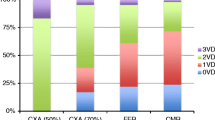

CA was performed in all patients without relevant complications. Coronary one-vessel disease (≥ 70% luminal narrowing) was observed in 15 [21%], two-vessel disease in 9 [12%] and three-vessel disease in 6 [8%]. Mean corrected TFC for the LAD was 21.5 ± 4.6 frames, for the LCX 33.0 ± 7.3 and for the RCA 25.9 ± 4.9.

In our study patients (only subendocardial perfusion deficit on CMR exam) no coronary stenosis ≥ 70% could be shown. In contrast, all control 2 patients (relevant perfusion deficit in CMR) had coronary stenoses as visualized by CA. A highly significant correlation between classification of CMR perfusion deficit and degree of coronary luminal narrowing was found (see table 2).

Corrected TFC in all coronary arteries was significantly increased in study patients compared to both controls groups: Study patients vs. control 1 (no perfusion deficit): 25.1 ± 4.9 frames vs. 20.9 ± 4.2 frames in the LAD, p = 0.002; 39.1 ± 7.7 vs. 30.1 ± 6.1 in the LCX, p < 0.0001; 29.1 ± 5.5 vs. 24.4 ± 3.8 in the RCA, p = 0.001) and vs. control 2 (relevant myocardial ischemia): 18.7 ± 2.0 in the LAD, p < 0.0001; 30.7 ± 4.5 in the LCX, p < 0.0001; 24.6 ± 4.5 in the RCA, p = 0.004 (figure 2). Prolonged corrected TFC (values above mean of control 1) were present in all 22 study group patients (per vessel analysis: in 60/66 (91%)), in contrast to control 2 patients (per vessel analysis: in 12/72 (17%)). A good correlation between corrected TFC in LAD and LCX was found in our study patients (κ = 0.87; 95% CI [0.72–0.95]; p < 0.0001). Corrected TFC in control 1 and control 2 patients showed a lower correlation for LAD and LCX (κ = 0.71; 95% CI [0.45–0.86]; p < 0.0001 and κ = 0.50; 95% CI [0.11–0.75]; p = 0.01), respectively (figure 3). No correlation between LAD and RCA or LCX and RCA TIMI frame count was observed, respectively.

Study patients had more often hypertension (15 [68%] versus 10 [37%], p = 0.03) and diabetes (9 [41%] versus 4 [15%], p = 0.04) than control 1 patients. Control 2 patients also had more commonly hypertension (16 [67%], p = 0.03) and diabetes (11 [46%], p = 0.02) than control 1 patients. Patient groups did not differ for hypercholesterolemia or smoking nor did study and control 2 patients differ for the above mentioned cardiovascular risk factors.